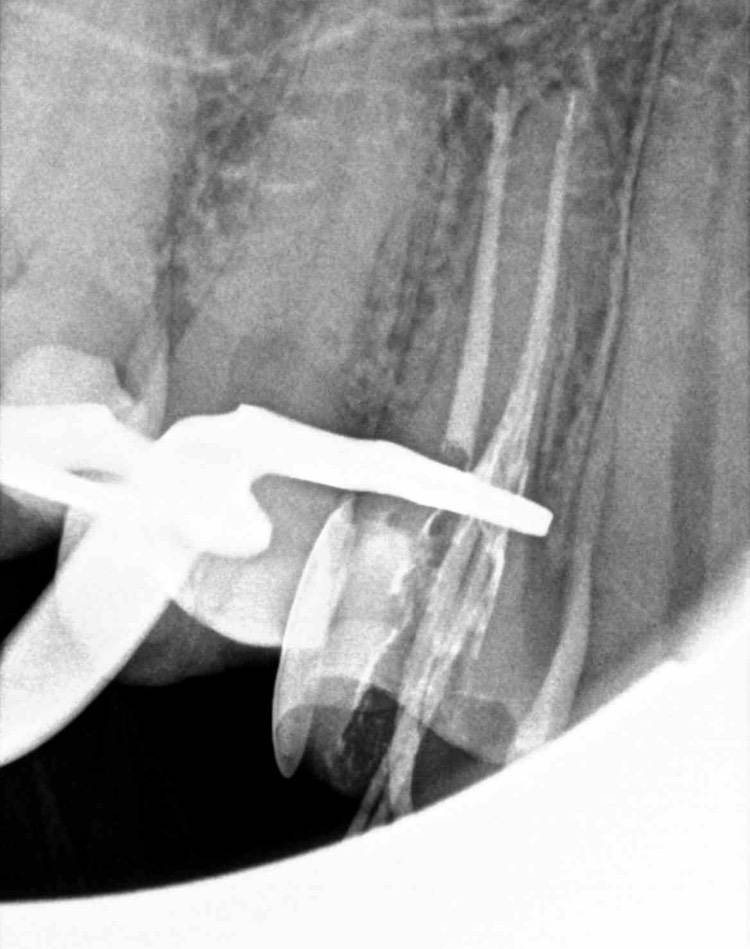

После удаления нервов у зума странная чувствительность когда касаешься наружной стенки водишь по ней ногтем … больновато сравнимо с оголенной шейкой зуба, на других поверхностях зуба норм. Снимки в хронологии прилагаю последний снимок спустя несколько месяцев94B0418C-0671-4347-824E-2BED80137804.jpeg.b4e6cccb387c9e1b58de0eb9e369f2d7.jpeg94B0418C-0671-4347-824E-2BED80137804.jpeg.b4e6cccb387c9e1b58de0eb9e369f2d7.jpeg924477BE-6116-4211-BAB9-431D846594C7.jpeg.8483250f5593afac6ce90d406c59f524.jpeg